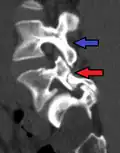

Anterolistesis L5/S1 -

Anterolistesis L5/S1. Flecha azul pars interarticularis normal. La flecha roja es una ruptura en pars interarticularis -

Anterolistesis L5/S1